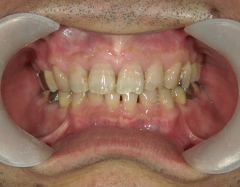

矯正歯科 治療前矯正歯科 治療前

矯正歯科 治療前 右上4番、左右下4番 計3本抜歯し、叢生を改善

no.22_8175_治療前_右.jpgno.22_8175_治療前_正面.jpgno.22_8175_治療前_左.jpg